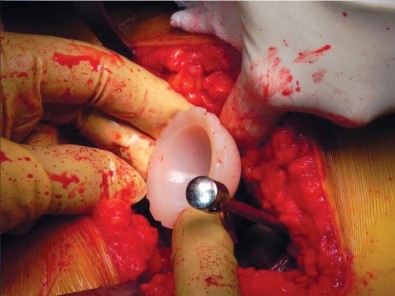

الزرعة نظام Taperloc Microplasty

يفضل الأستاذ الدكتور محمد هطيف استخدام نظام Taperloc® Microplasty من شركة Biomet (وارسو، إنديانا)، وهو أحد الخيارات المتاحة للزرعات الخالية من الأسمنت. يعتمد هذا النظام على تصميم إسفيني مخروطي وسطي-جانبي بدون ياقة، مصمم للتثبيت الذاتي والاستقرار الدوراني.

- المادة والتصميم: مصنوع من التيتانيوم (Ti-6AL-4V) ويتميز بطلاء مسامي رش بلازما محيطي قريب. تستخدم Biomet تقنية خاصة لتطبيق الطلاء المسامي بحيث لا يتم تسخين الزرعة بشكل كبير، مما يحافظ على مستويات عالية من مقاومة الإجهاد.

- الأحجام والتنوع: تتوفر السيقان في أحد عشر حجمًا، تتراوح أطوالها من 95 ملم إلى 130 ملم، وتزداد تدريجيًا جانبيًا بينما يظل الانحناء الأنسي ثابتًا. زاوية عنق-جذع 138 درجة، وهناك خياران للإزاحة: قياسي وجانبي.

- تقنية التحضير: باستثناء موسع الفتحة، لا يتطلب النظام أي كشط؛ فهو نظام يعتمد على التوسيع فقط، مما يسهل الإجراء ويقلل من إزالة العظام.

تحضير الفخذ والحق

يتم تحديد مستوى قطع عنق الفخذ مسبقًا بالتخطيط (باستخدام الأشعة السينية) ومواءمته أثناء الجراحة مع المدور الكبير. بعد قطع عنق الفخذ، يتم تحضير الحُق بالطريقة القياسية قبل تحضير الفخذ. يفضل الأستاذ الدكتور محمد هطيف عادةً وضع الكأس وفقًا للمعالم التشريحية لإعادة إنشاء التوجيه الطبيعي للحُق لدى المريض ويتحقق من الإصدار والميل الصحيحين عن طريق الجس والرؤية المباش